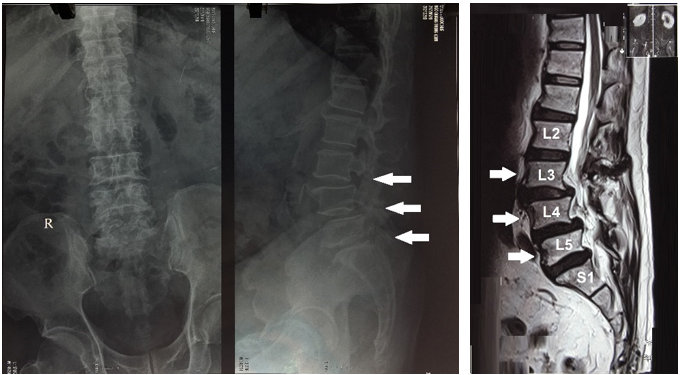

Bệnh nhân nam 63 tuổi vào viện vì đau tê và rối loạn cảm giác vùng quanh hậu môn kèm tiểu khó 2 tuần nay, các triệu chứng tăng dần tới thời điểm thăm khám. Tiền sử: bệnh thận mạn (CKD) đang điều trị với corticoid 10-15 viên/ngày, tăng huyết áp đang điều trị 1 năm nay, hen phế quản 4 năm. Thăm khám thực thể: đau vùng cột sống thắt lưng lan xuống hai chân, điểm VAS đau cột sống thắt lưng 9/10 rối loạn đại tiểu tiện (tiểu khó, đại tiện khó), cơ lực chân phải 4/5, chân trái 4/5; hình ảnh X quang (Hình 1a), CT scan, MRI vùng cột sống thắt lưng cho thấy gai xương L3, L4, L5, giảm chiều cao thân đốt sống L4, L5, khuyết eo L3, L4, L5 gây trượt thân đốt sống L3, L4 ra trước độ I (Hình 1b), phình đĩa đệm L3-4 chèn ép rễ thần kinh L3 hai bên đoạn trong lỗ liên hợp, phình đĩa đệm tầng L4-5 chèn ép rễ thần kinh L4 bên trái đoạn trong lỗ liên hợp, thoái hóa đa tầng đĩa đệm cột sống thắt lưng. Bệnh nhân đã có triệu chứng rối loạn cơ vòng kèm các dấu hiệu thần kinh tăng nặng lên nên chúng tôi quyết định phẫu thuật PLIF: cố định cột sống bằng vít qua cuống tại L3-S1 và đặt hai mảnh ghép liên thân (PEEK) tại L3-4, L4-5. Trước khi tiến hành phẫu thuật, bệnh nhân được điều trị ổn định huyết áp, ổn định đường huyết, kiểm soát cơn hen phế quản.

Hình 1. Hình 1a. Xquang cột sống thắt lưng thẳng-nghiên, Hình 1b. MRI vùng cột sống thắt lưng cho thấy gai xương L3, L4, L5, giảm chiều cao thân đốt sống L4, L5, khuyết eo L3, L4, L5 gây trượt thân đốt sống L3, L4 ra trước độ I.